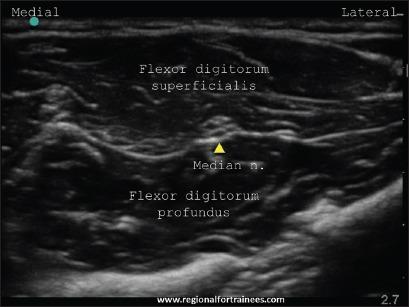

Upper extremity surgery is commonly performed under regional anesthesia. The advent of ultrasonography has made performing upper extremity nerve blocks relatively easy with a high degree of reliability. The proximal approaches to brachial plexus block such as supraclavicular plexus block, infraclavicular plexus block, or the axillary block are favored for the most surgical procedures of distal upper extremity. Ultrasound guidance has however made distal nerve blocks of the upper limb a technically feasible, safe and efficacious option. In recent years, there has thus been a resurgence of distal peripheral nerve blocks to facilitate hand and wrist surgery. In this article, we review the technical aspects of performing the distal blocks of the upper extremity and highlight some of the clinical aspects of their usage.

上肢手术通常在区域麻醉下进行。超声检查的出现使得进行上肢神经阻滞相对容易,且可靠性高。对于大多数上肢远端的外科手术,臂丛神经阻滞的近端入路,如锁骨上神经丛阻滞、锁骨下神经丛阻滞或腋路阻滞,是比较常用的。然而,超声引导使得上肢远端神经阻滞成为一种技术上可行、安全且有效的选择。近年来,远端周围神经阻滞因此再度兴起,以方便手部和腕部手术。在本文中,我们回顾了进行上肢远端阻滞的技术要点,并强调了其使用的一些临床方面。